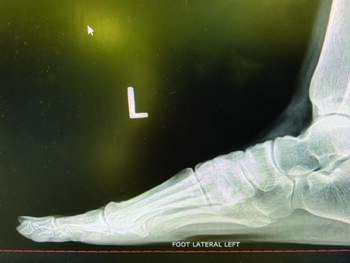

Standard radiographs allow further assessment of the bunion deformity, including anterior-posterior, medial oblique, and lateral weight-bearing. Further imaging may be necessary, and a sesamoid axial view looks at sesamoid position and frontal plane rotation of the metatarsal head as needed. Finally, in certain complicated or difficult cases that may have additional imaging needs, weight-bearing CT (computerized tomography) may help visualize the deformity in a three-dimensional fashion.